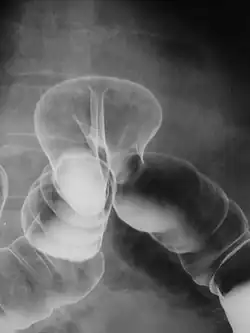

Röntgenaufnahme eines Patienten mit einer Hernie von Kolon durch eine Zwerchfelllücke

Bei der Zwerchfellhernie (lateinisch Hernia diaphragmatica) gelangen Bauchorgane in die Brusthöhle.